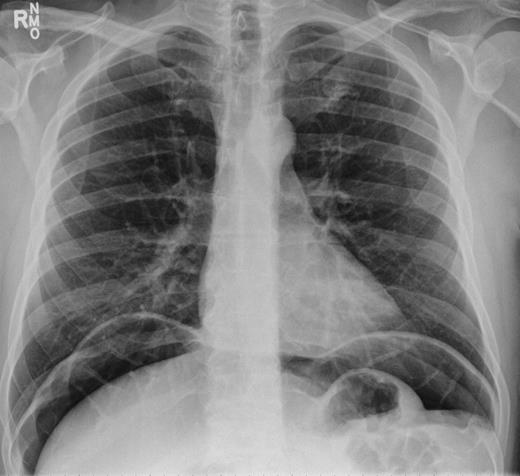

Over a year later, the same gentlemen presented to the surgical admissions unit once again with a history of acute abdominal pain. The duration and nature of symptoms were very similar to his previous admission. He again underwent plain film abdomen and erect chest radiographs that showed a large volume of free air under the diaphragm (Figs. 4 and 5).